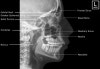

4) Adult Mandible - Orthopantogram (OPG)

(1) The Orthopantomogram (OPG) is a panoramic view of the mandible.

(2) Structures crossing over the mandible can be distracting. For example, the air-filled oropharynx is often seen as a smooth black line passing across the mandible.

(3) Carefully following the cortical outline of the mandible shows no fracture.

(4) The mandible has varying appearance according to the developmental stage of teeth.